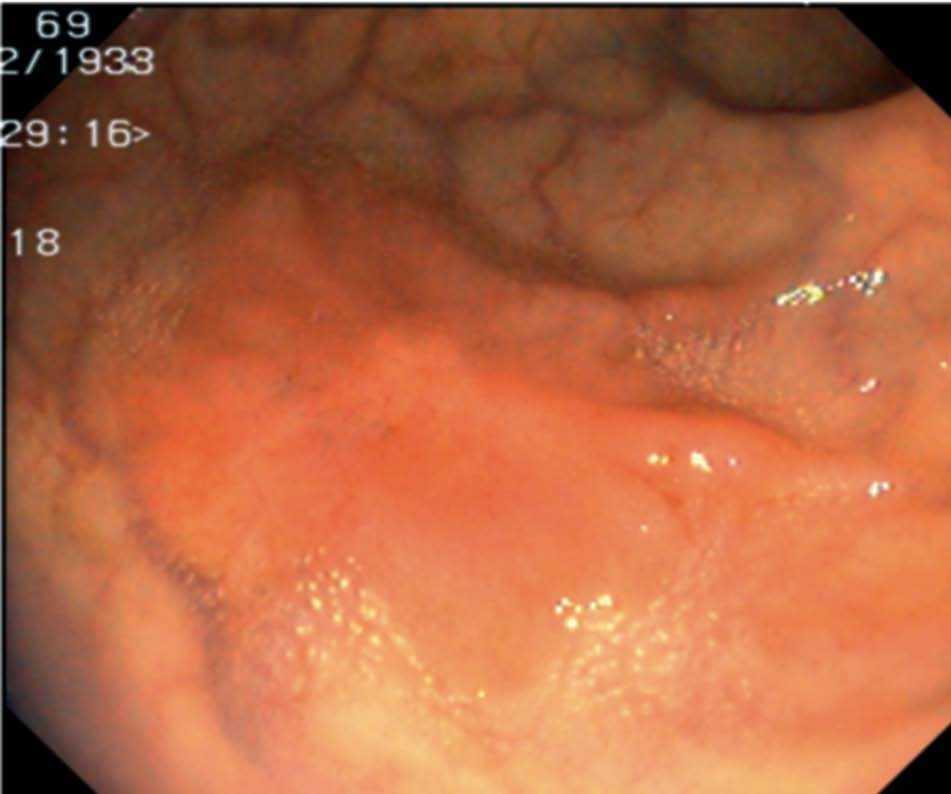

Fig. 3. Examples of flat lesions with conventional examination and after the application of indigo carmine 0.2-0.5%. a, b) Small flat adenoma, 3 mm in size. c, d) Large flat adenoma, 15 mm in size. e, f) Completely flat lesion (IIb in the Japanese classification). g, h) Depressed lesion, 3 mm in size) (IIc in the Japanese classification). I, J) Depressed lesion, 7 mm in size, histopathological study revealed submucosally invasive cancer (traditionally IIc in the Japanese classification, although recently such depressed lesions with a distinct central protrusion indicating submucosal invasion are termed IIc + Is). k, l) Flat elevated lesion with central depression, 10 mm in size, corresponding to a submucosally invasive cancer (IIa + IIc in the Japanese classification).